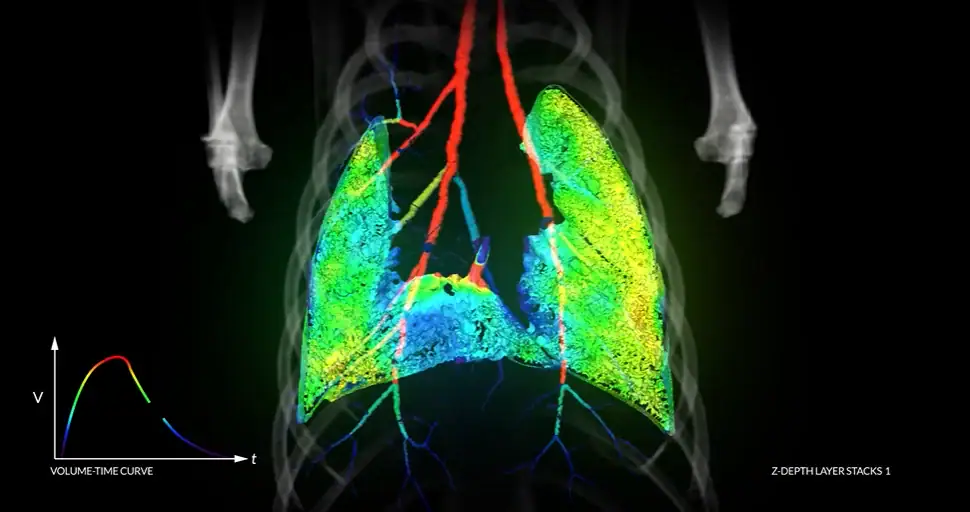

The XV Scanner integrates 4DMedical’s proprietary XV Technology™ software with purpose-built hardware, providing doctors and patients with unprecedented and highly visual insight into respiratory function via automated scans.

This unique and transformative XV TechnologyTM accurately and quickly scans lung function as the patient breathes, enabling early diagnosis and the monitoring of changes over time.

“In less than 10 seconds and for less radiation than one chest X-ray, you can get a full four dimensional scan of somebody’s lungs while they breathe,” Fouras explained.

“The scanner allows you to see in rich detail where the air is going in the lungs, and where the air isn’t going – which is exactly what the doctors want to see,” Fouras said

It enables highly-detailed maps of both the patterns of lung motion and pulmonary function, with functional deficits detected through local (regional) differences in movement.